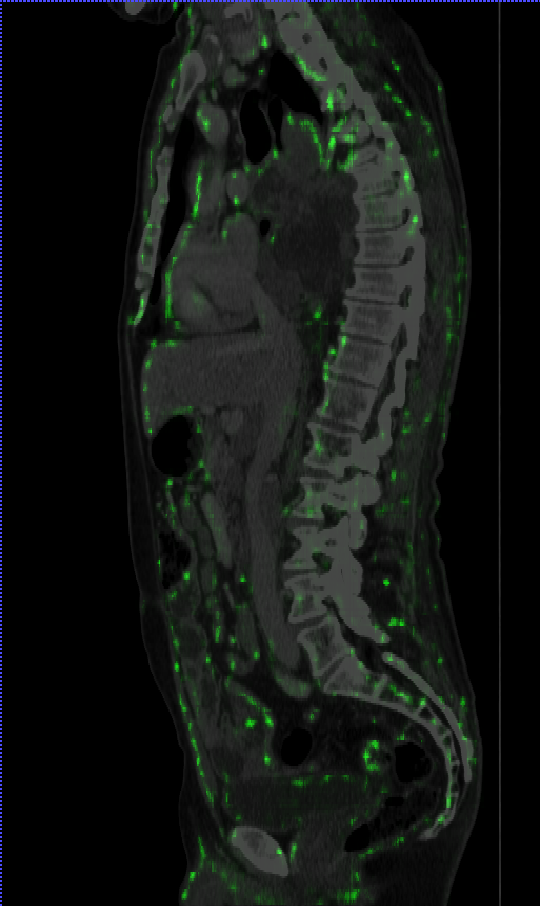

Thèse: "Détection et description de points clés dans des images medicales 3D, via des Réseaux neuronaux". Superviseurs: S. Valette, R. Kechichian. Travaux sur le Deep Learning pour l'extraction et la description de points clés dans des images CT-Scan 3D. Tests effectués sur la machine HPC du CNRS avec GPUs.

Thesis: "Detection and Description of Keypoints in 3D medical images". Advisors: A. Bartoli, S. Valette, R. Kechichian. Deep Learning work for keypoint extraction and description in 3D CT-Scan images. Tests performed on CNRS HPC machine with GPUs.

Conception d'algorithmes Deep Learning pour l'imagerie médicale 3D. Traitement de plus de 10 000 images CT-Scan sur infrastructure HPC (GPUs). Collaboration avec des équipes multidisciplinaires (médecins, ingénieurs, chercheurs).

Design of Deep Learning algorithms for 3D medical imaging. Processing of over 10,000 CT-Scan images on HPC infrastructure (GPUs). Collaboration with multidisciplinary teams (doctors, engineers, researchers).